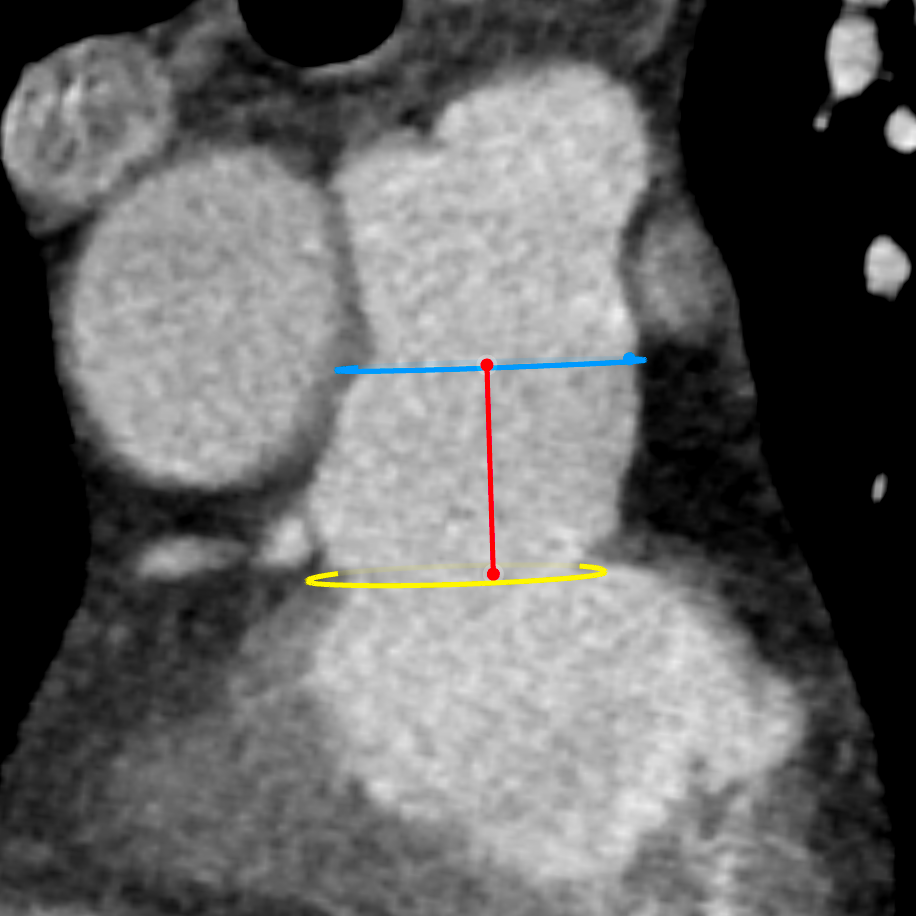

术中测量患者基础主动脉、肺动脉、右心室压力分别为111/58mmHg、31/4/13mmHg、34/1/6mmHg,通过肺动脉造影,术中测量球囊内径为32mm(见图二),选择36-25mm VENUS-P肺动脉瓣膜,在肺动脉造影指引下逐步打开瓣膜。考虑到患者肺动脉分叉较短,存在瓣膜释放后移位风险,故选择高位释放法(图三)。但释放瓣膜后造影提示右肺动脉开口局部被阻挡(图四),复测患者主肺动脉、左肺动脉、右肺动脉压力分别为57/13/25mmHg、55/12/24mmHg、27/7/14mmHg。

图二:术中扩张球囊刚好堵住右室流出道,测量球囊内经为32mm